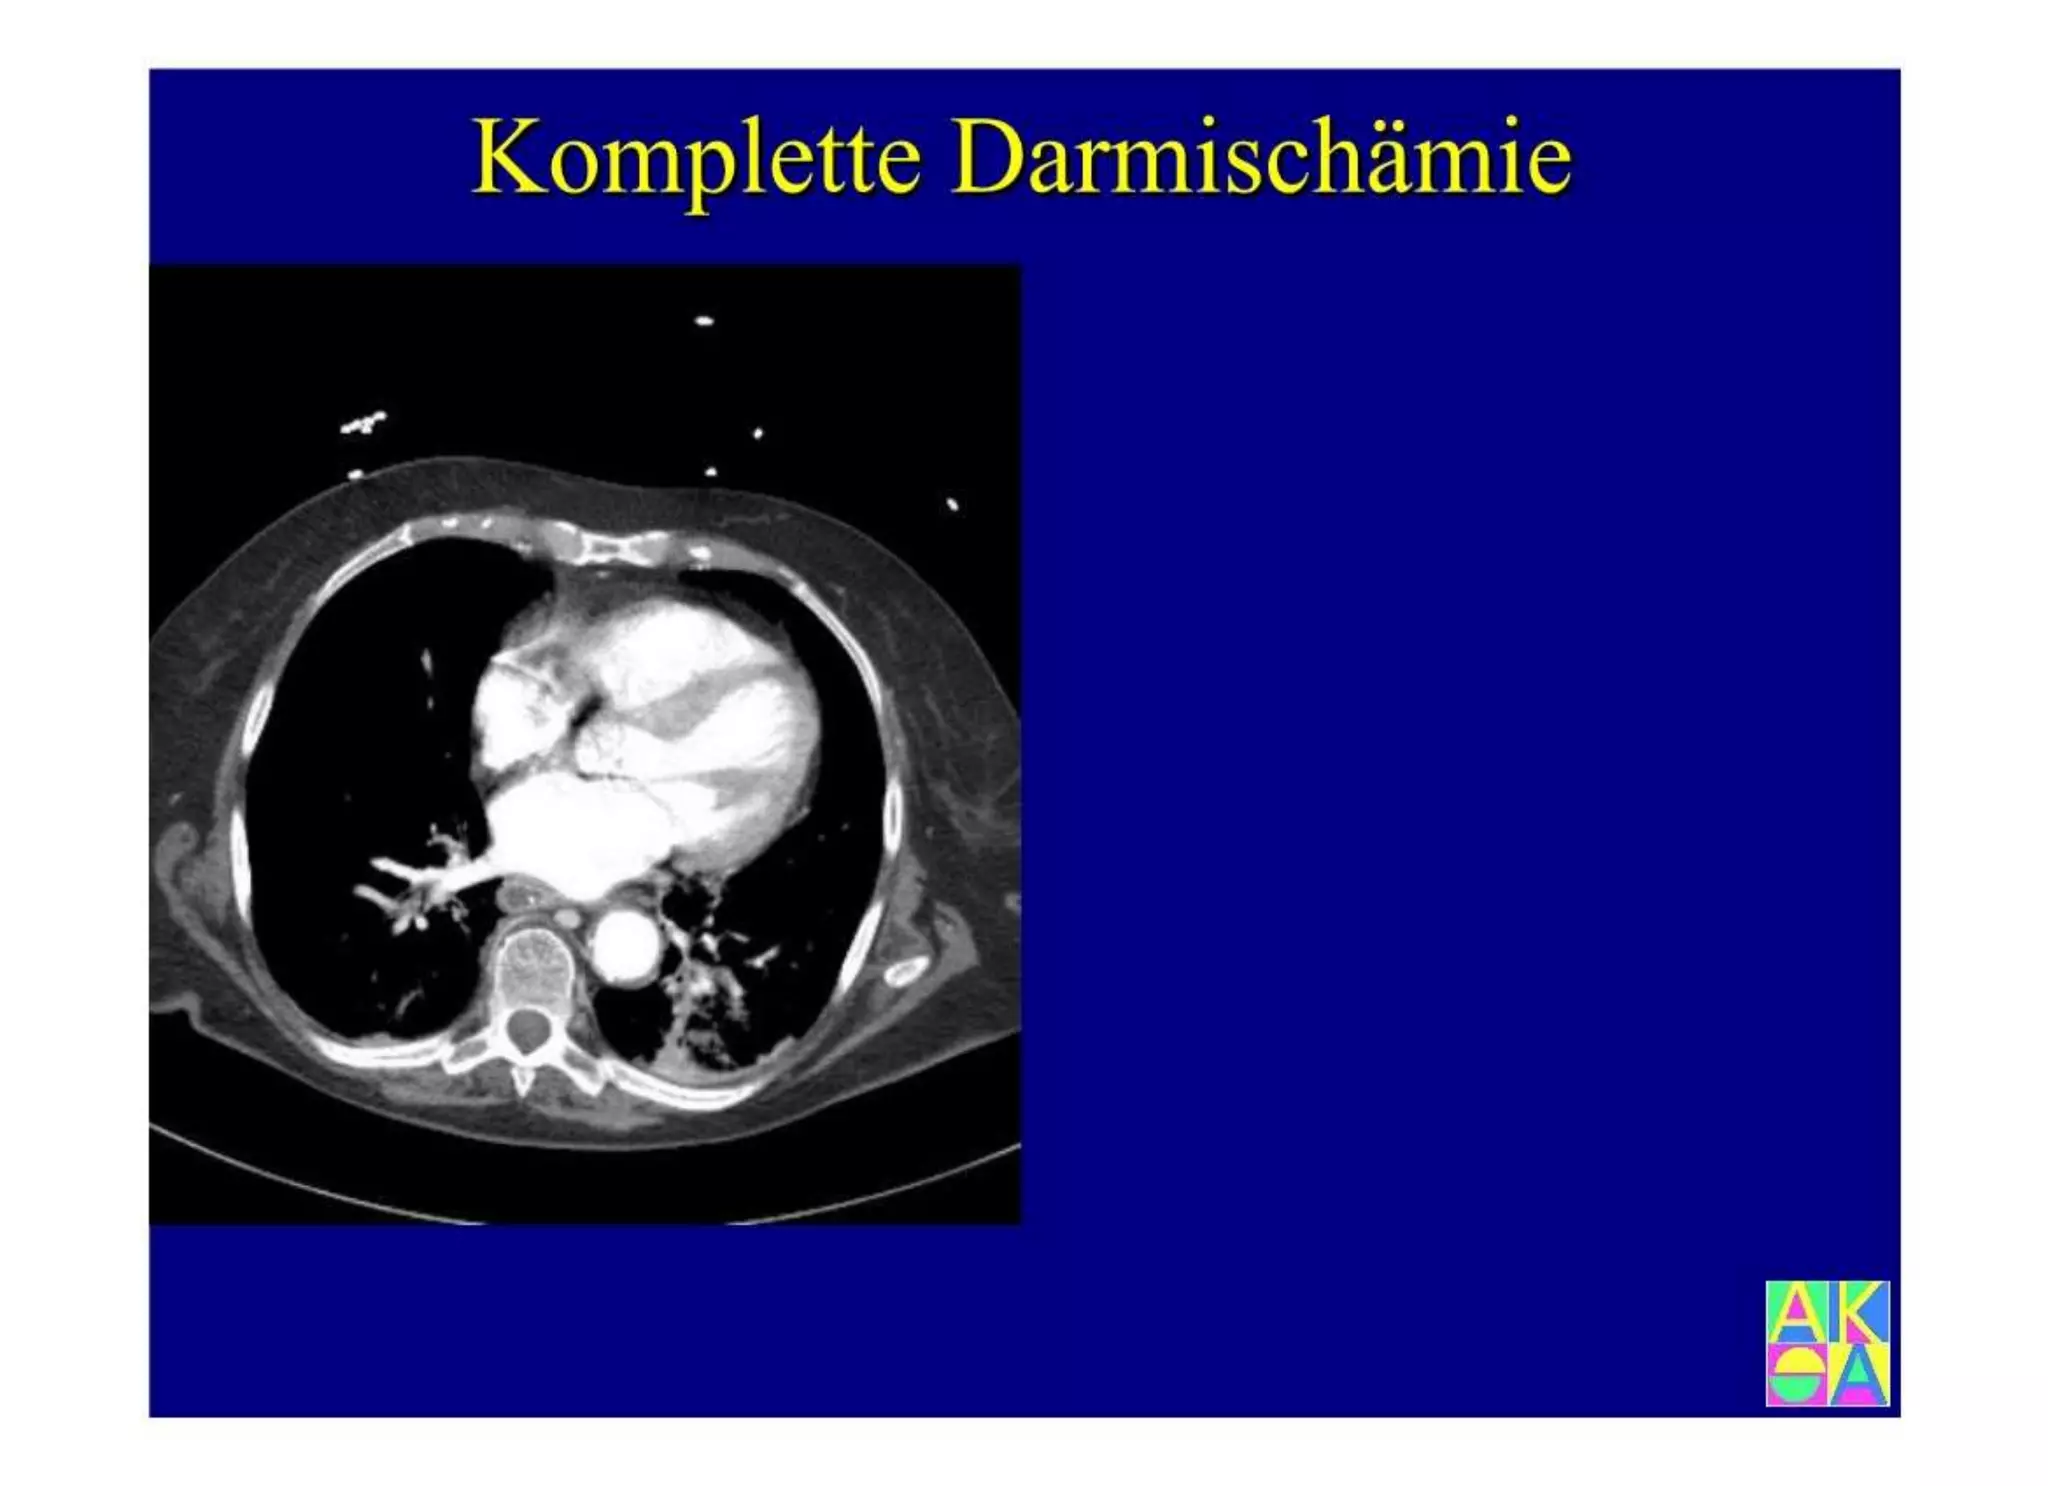

Chronische Enteropathie und Ileus, Dünndarm und Dickdarmdiagnostik, Mechanischer und paralytischer Ileus, Eingeklemmte Darmabschnitte, aufgereihter Bridenileus, und dazu Dickdarmileus, eingeklemmte Hernien, Weitergabeskript